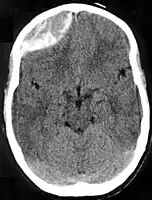

Diagnosis is typically by CT scan or MRI.[1] MRIs have greater sensitivity and should be used if there is a high suspicion of epidural hematoma and a negative CT scan.[3] Differential diagnoses include a transient ischemic attack, intracranial mass, or brain abscess.[3]

Epidural hematomas usually appear convex in shape because their expansion stops at the skull's sutures, where the dura mater is tightly attached to the skull. Thus, they expand inward toward the brain rather than along the inside of the skull, as occurs in subdural hematomas. Most people also have a skull fracture.[3]

Epidural hematomas may occur in combination with subdural hematomas, or either may occur alone.[11] CT scans reveal subdural or epidural hematomas in 20% of unconscious people.[16] In the hallmark of epidural hematoma, people may regain consciousness and appear completely normal during what is called a lucid interval, only to descend suddenly and rapidly into unconsciousness later. This lucid interval, which depends on the extent of the injury, is a key to diagnosing an epidural hematoma.[3]